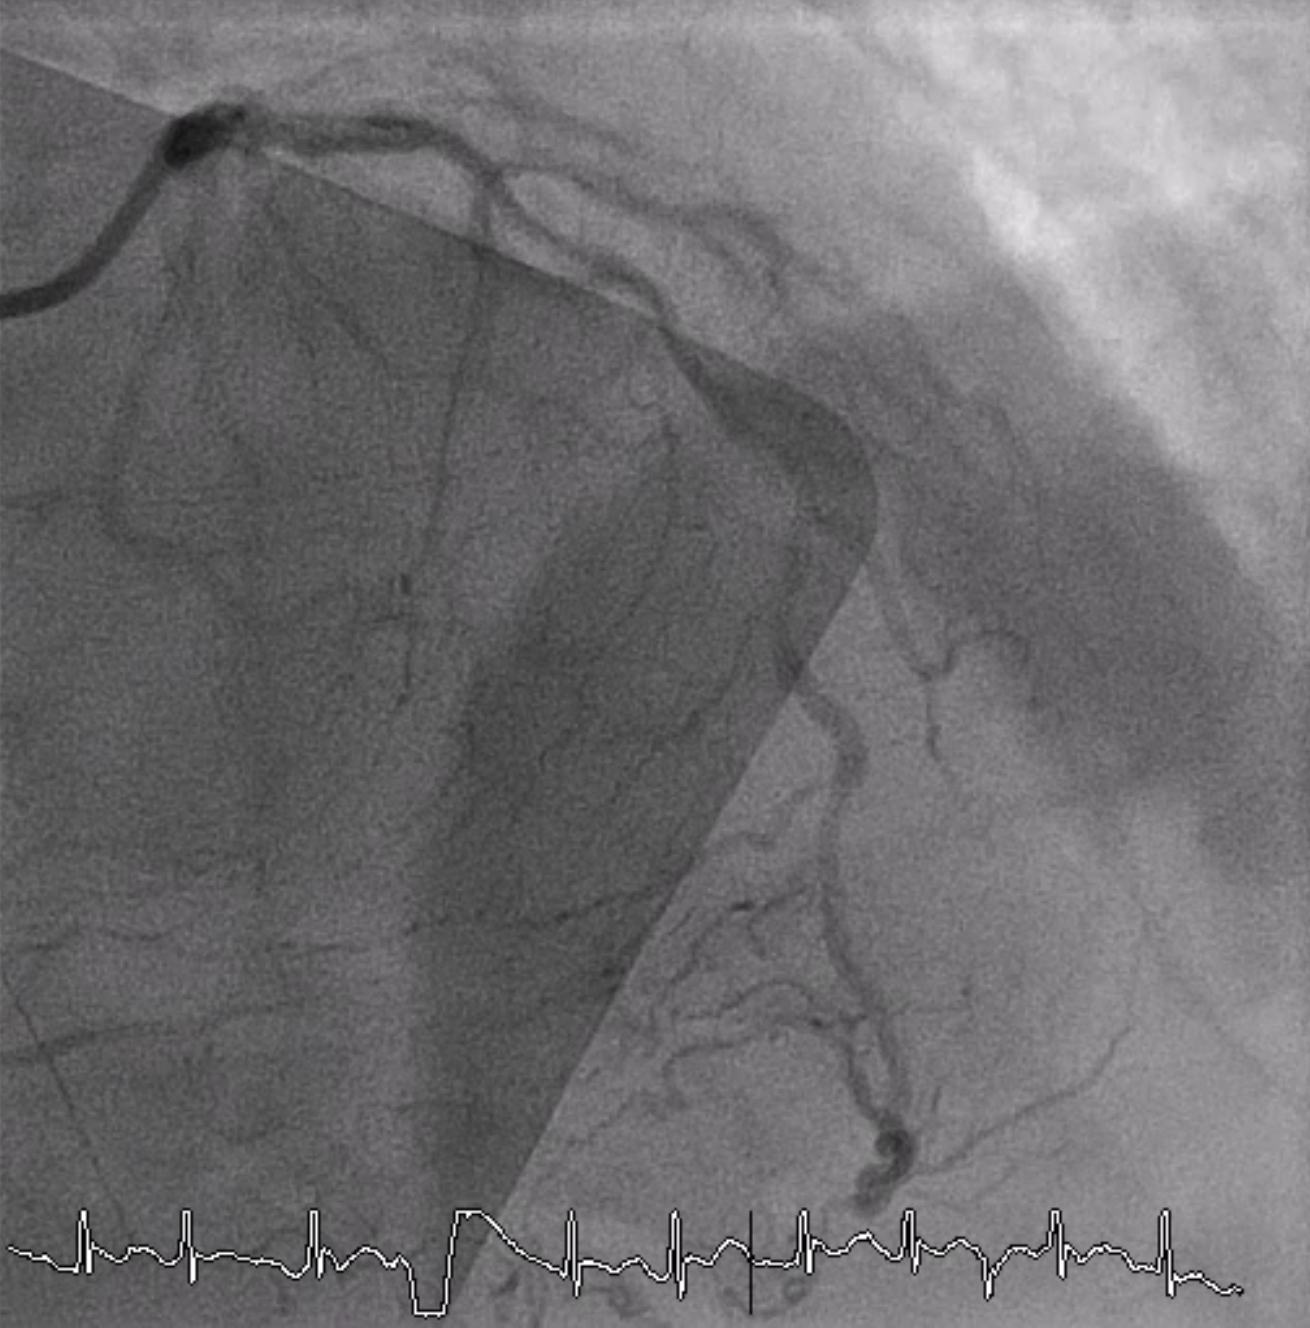

Relevant Catheterization Findings

Coronary angiography revealed total occlusion at proximal RCA with collateral circulation from conus branch, LAD and LCx to RCA. 70-80% stenosis at proximal to mid LAD and 50% stenosis at distal Lcx and OM.

A 6 Fr JR 4.0 guiding catheter was engaged via femoral approach and JL 4 catheter was used for dual injection. We planned to perform PCI at proximal RCA CTO with antegrade wire escalation technique first. We successful wired to PL branch of RCA using microcatheter with Gaia Next 2 guidewire (Failed using Fielder XT). The microcatheter could not cross lesion. Try using CTO balloon 0.75/8 mm and 1.0/6 mm to pre-dilatation but still uncrossable. So we put the microcatheter farthest and successful bare wiring the RotaWire Floppy to PL. Rotational atherectomy was done with Burr 1.25 mm at 172,000 - 146,000 rpm total 4 runs. IVUS was pulled back from PL-RCA showed intra-plaque wiring, calcified nodules with cracked calcific plaques and reverberation. We prepared the lesion proximal to mid RCA lesion with non-compliant 2.5/15 mm balloon at 20 atm and scoring 3.0/13 mm balloon at 18-20 atm. A 3.0/38 mm stent could not be delivered the lesion. We used the guide extension catheter with balloon-assisted tracking techinque for delivery. The stent was successfully deployed to mid RCA. The 3.5/28 mm stent was deployed to proximal to mid RCA and 3.5/18 mm stent was deployed at ostial RCA. Post-dilatation with non-compliant 3.0/15 and 3.5/18 mm at 16 atm. Final angiogram showed good coronary blood flow and IVUS demonstrated well stent expansion, no malapposition and no stent edge dissection.